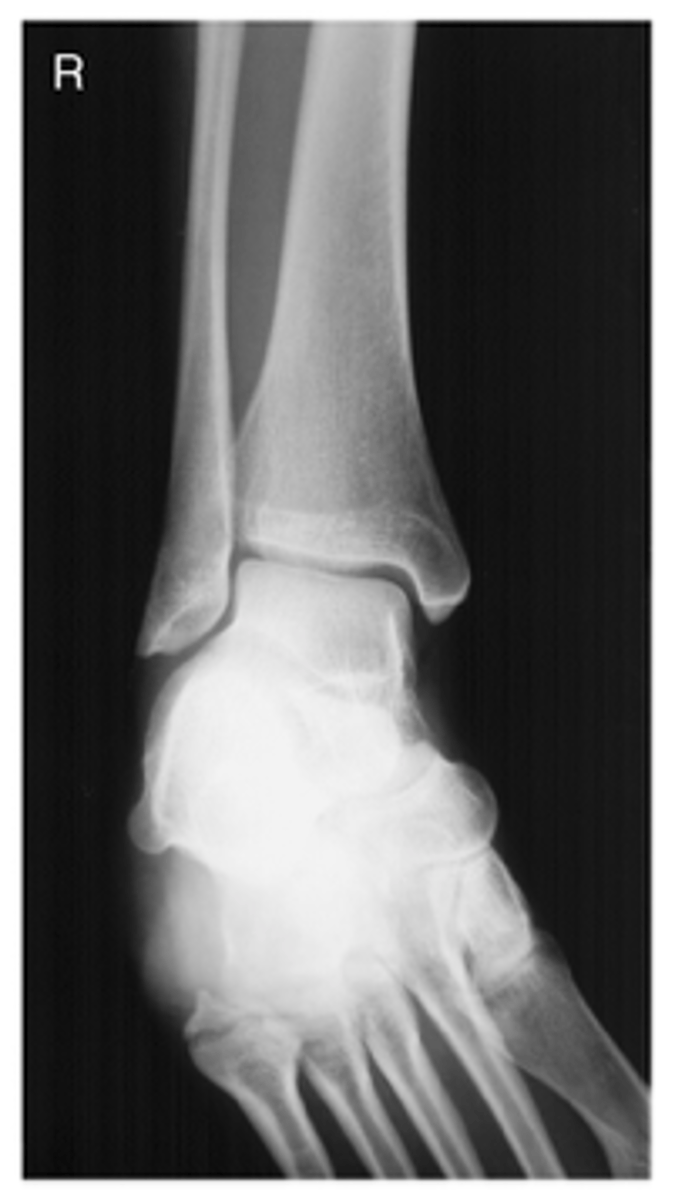

AP Stress Ankle (Inversion)

What projection is this?

AP Stress Ankle (Eversion)

Evaluation Criteria AP Stress Ankle

- Distal aspect of tibia and fibula demonstrated

- Ankle joint to center of collimation field

- Optimal exposure factors